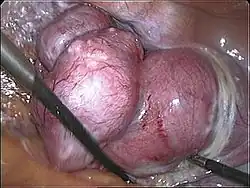

Uterus prior to hysterectomy

Uterus prior to hysterectomy -